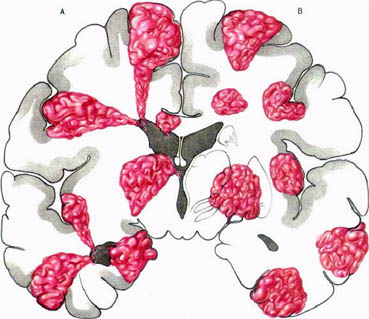

A tipikus lokalizáció agyi arteriovenosus rendellenességek.